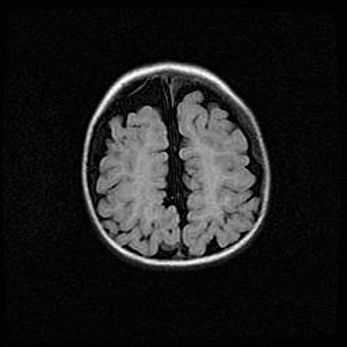

Неполная лизэнцефалия (пахигирия). Открытая гидроцефалия.

Возраст: 17 дней

Вес: 3110 г

Пол: мужской

Окружность головы: 33,5 см

Срок гестации: 35-36 недель

Лизэнцефалия—недоразвитие корковой пластинки и мозговых извилин в результате нарушения миграции нейронов коры. Поверхность мозговых полушарий гладкая. Микроскопически выявляется отсутствие нормальных слоев коры и скопление групп нейронов в подкорковом белом веществе.

Пахигирия—уменьшение числа вторичных извилин. В пораженном полушарии нервные клетки образуют толстый недифференцированный слой с неправильно расположенными нервными волокнами и группами гетеротопных клеток. Нервные клетки незрелые. Белое вещество истончено. При этом нередко аномально развит корково-спинномозговой путь.